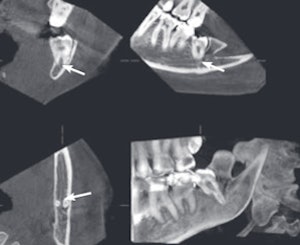

An example of cone-beam CT. In this instance, the lower left third molar (d. 38) was imaged after panoramic radiograph with CBCT. The arrows mark the mandibular canal. Images courtesy of Dr. Anni Suomalainen.